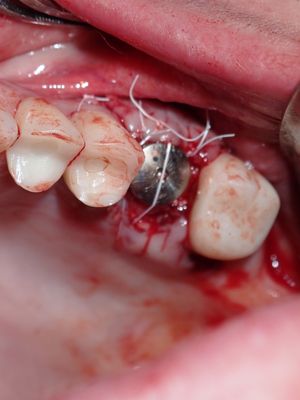

atraumatic exo 26, no loss of labial or palatal plate. Softer bone, implant osteotomy underprepared, difficult/impossible to stretch palatal flap, about 1.5mm exposued at palate, fibrin mmebrance placed on crest, socket grafted with sticky bone from 90/10 mix of mineralized cortical/xenograft